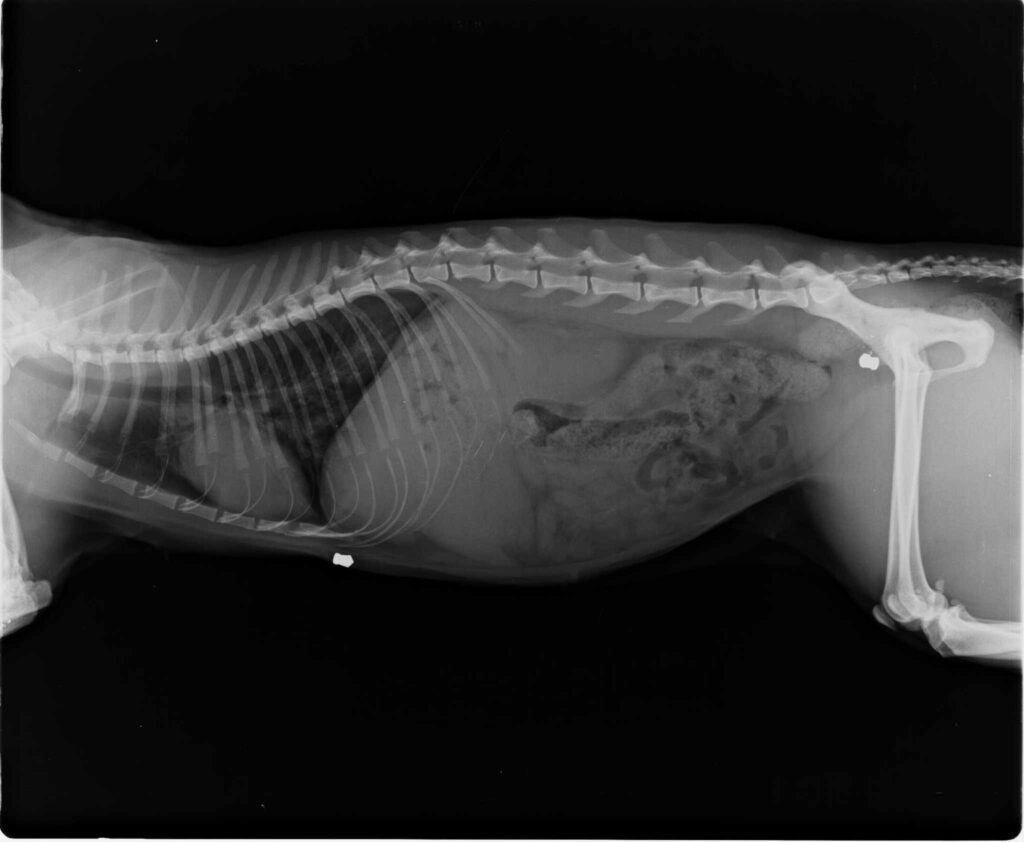

Όπως κάνει γνωστό η Φιλοζωική Ομάδα Βόλου “Κάποιος ψυχικά ασταθής ζει ανάμεσα μας, και πυροβολει αβέρτα γάτες, πιο συγκεκριμένα ο ψυχακιας αυτός ζει στα Πλατανιδια Βόλου, και τα θύματα του είναι συνήθως γάτες που κυκλοφορούν στην παραλία Πλατανιδίων. Έχουν ήδη ενημερωθεί οι αρχές, και περιμένουμε για τον εντοπισμό του δράστη. Ανοίξτε τα στόματα σας, σήμερα είναι γάτες αύριο ίσως εσείς.

- Είναι ασταθής κι επικίνδυνοι αυτοί οι άνθρωποι. Έχει αποδειχθεί άλλωστε αμέτρητες φορές με θυμάμαι ανθρώπους και ζώα. Ανοίξτε τα στόματα σας προτού να είναι αργά. Αν έχετε πληροφορίες ή υποψίες μπορείτε να επικοινωνήσετε με το αρμόδιο αστυνομικό Μέγαρο Βόλου”.